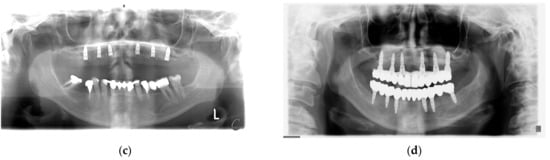

2. Case Report

| Measurements in mm | R1 | R2 | R3 | L1 | L2 | L3 | Avg | Avg Change (%) |

|---|---|---|---|---|---|---|---|---|

| Initial situation | 7.06 | 6.3 | 2.72 | 5.85 | 4.2 | 6.74 | 5.48 | |

| Post augmentation (6 months) | 12.04 | 11.71 | 10.64 | 12.11 | 10.72 | 11.27 | 11.42 | 47.9 |

| Follow up (6 years) | 9.47 | 9.97 | 6.03 | 9.72 | 9.47 | 9.13 | 8.97 | −21.4 |